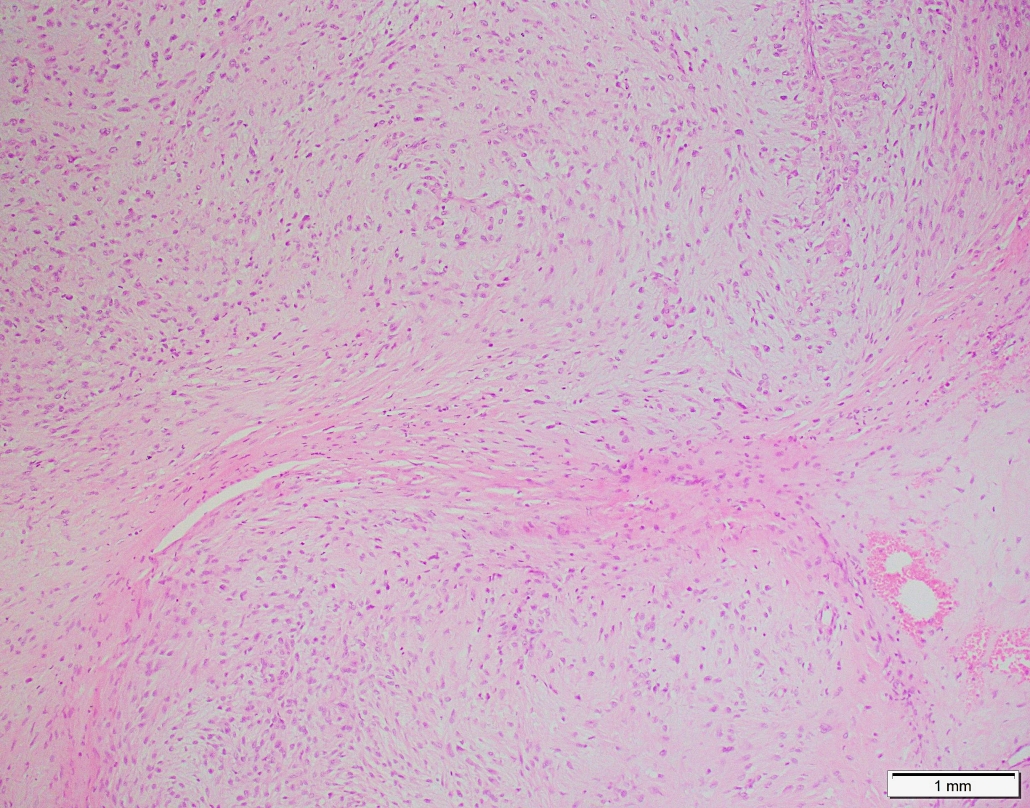

45 years old male with a chest wall soft tissue mass.

Choose correct option: *Sclerosing epitheliod fibrosarcomaMyxofibrosarcomaNodular FascitisLow grade fibromyxoid sarcomaMyoepithelial Neoplasm